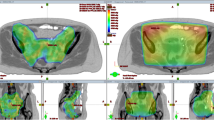

The boxplots in Fig. 2a summarize the average measured T50 and registered time intervals for the cohort of 58 patients. The median average measured T50 and time interval were 41.2 °C (range 39.7–42.5 °C) and 79 min (range 34–125 min), respectively. Calculation of the dose enhancement for all treatment sessions resulted in a median total enhancement in equivalent D50 of 5.5 Gy (interquartile range [IQR] 4.0–6.6 Gy) to the physical 46–50.4 Gy radiation dose.

a Clinical measurement data (target temperatures and time intervals) registered for 58 patients with locally advanced cervical cancer treated with radiotherapy plus hyperthermia. These data were used as input for biological treatment evaluation to determine the effective total dose enhancement over the full treatment course. b Evaluation of the expected impact of changes in treatment logistics on the dose enhancement. A 30-min time interval reflects optimized logistics, while a 4‑h time interval represents worst-case suboptimal logistics (e.g., in case of long travelling distances). The shaded areas correspond to the interquartile ranges (IQR) for the real time intervals from a for easy comparison. EQDRT Equivalent radiation dose. T50 The temperatures at least achieved in 50% of the measurement points during the steady-state period

Figure 2b shows the expected impact of very optimal logistics (tint = 30 min) and suboptimal logistics (tint = 4 h) compared to the real time intervals. A time interval of 30 min for all treatment sessions would significantly increase the D50 dose enhancement by ~30% to 7.1 Gy (IQR 5.5–8.1 Gy; p < 0.001). In case of 4‑h time intervals, an ~ 40% decrease in dose enhancement could be expected: 3.2 Gy (IQR 2.3–3.8 Gy; p < 0.001).